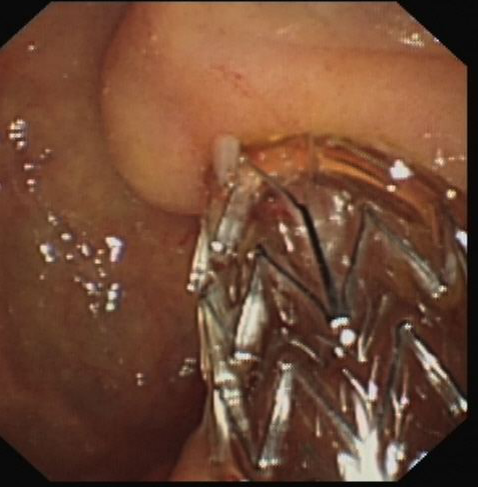

胆道疾病诊疗:主要以现代内镜外科为特色,通过微创手术的方法解决胆道疾病,利用十二指肠镜(治疗性ERCP)、胆道镜来完成的,大部分常见胆道疾病都是治疗性ERCP的适应证,如胆道结石、梗阻性黄疸、胆道蛔虫、胆道肿瘤、胆源性胰腺炎等。能极大避免胆道结石的残留与复发;同时,我科积累了上千例的腹腔镜胆囊切除(LC)的经验,还开展了腹腔镜肝叶切除、肝囊肿开窗引流、胆总管切开取石、胆道探查、胆总管切开I期缝合等手术,形成了自己的特色。对于晚期胆道肿瘤,通过胆道支架置入,提高了患者的生存质量;能早期解除胆源性胰腺炎的病因,降低了急性重症胰腺炎的死亡率。对复杂型肝胆管结石症、多发性肝内胆管结石采用手术中纤维胆道镜、超声定位、冲击波碎石等方法并用,对肝胆管结石进行彻底清除,大大减少了残石率及再发率。